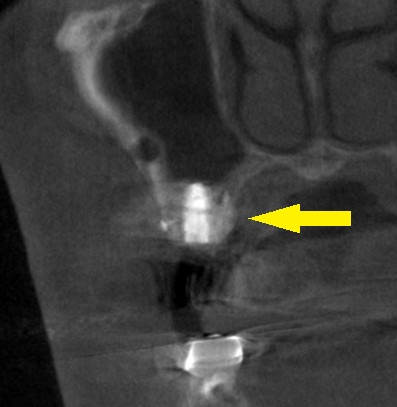

下の写真、下段右が手術後のCTです。

インプラントの内側に人工骨が補填され、白く写っています。